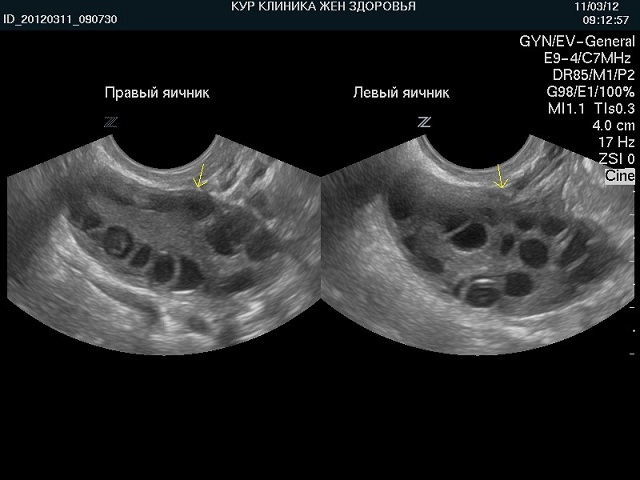

Подтверждение синдрома поликистозных яичников основывается на наличии у пациентки специфических признаков этого заболевания. Часто наблюдаются сочетания различных симптомов. Множество факторов может привести к бесплодию, поэтому для установления диагноза необходимо провести комплексное обследование. Гинекологический осмотр позволяет пальпаторно определить увеличение яичников и их болезненность. Изменения в размерах половых желез подтверждаются с помощью ультразвукового исследования органов малого таза. На снимках, полученных в ходе этого обследования, яичники имеют характерный вид, внутри них видны полости, заполненные жидкостью — кисты. Капсула яичников становится более плотной, а местный кровоток усиливается. Ультразвуковая диагностика обладает высокой информативностью при подозрении на поликистоз, поэтому широко используется специалистами. Кроме визуальных изменений, в ходе лабораторных исследований фиксируется повышенная секреция андрогенов и гонадотропных гормонов. В некоторых случаях также наблюдается увеличение уровня кортизола, вырабатываемого корой надпочечников, что зависит от причины заболевания. Для исключения возможности опухолевых процессов в половых железах необходимо провести МРТ и лапароскопию, что позволит точно оценить состояние желез и взять образцы для гистологического анализа.